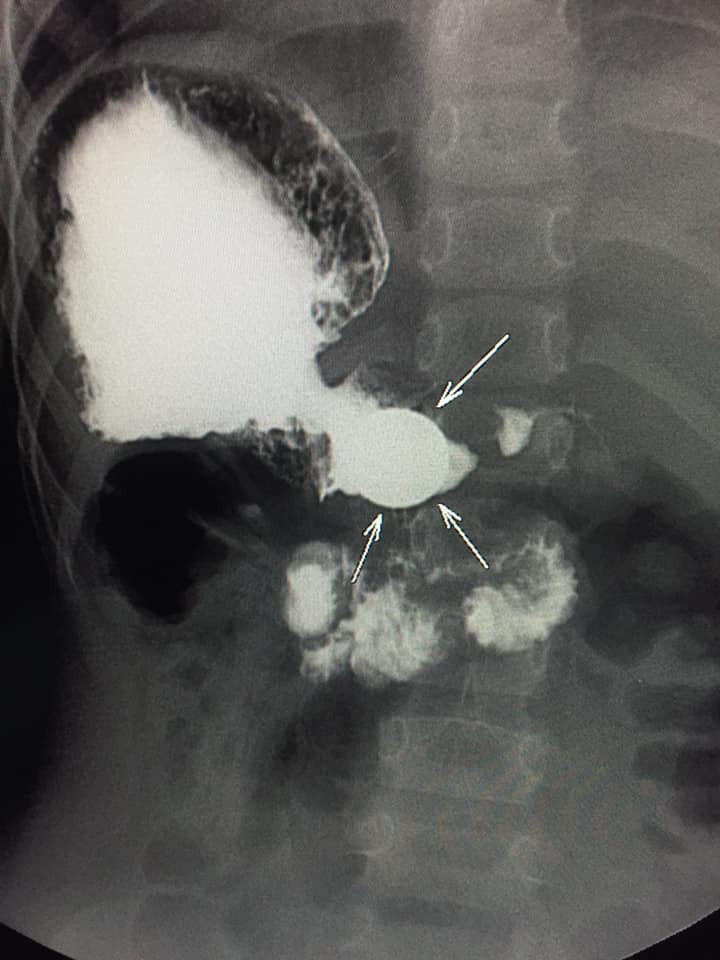

Azyaşlının mədəsində tapılan qəpiyin fotolarını təqdim edirik: